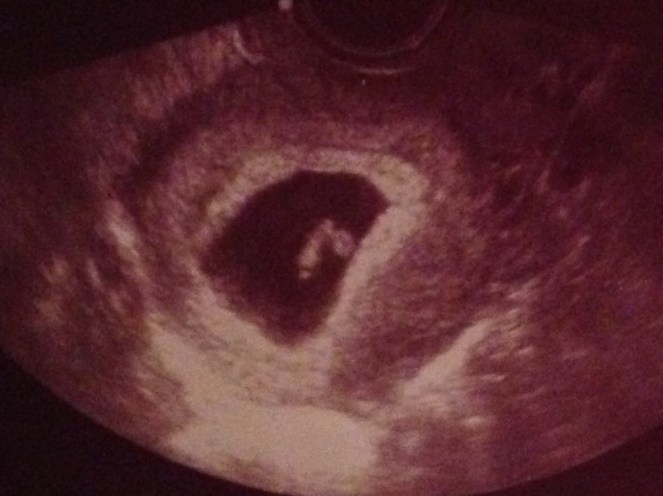

This is my daughter. She was 6 weeks, 3 days. She already had a beating heart that was strong and clear. It was incredible to hear her heart beating within the safety of my womb. It was a miracle.

I share this because I want people to see what human life looks like even at just 6 weeks into pregnancy. At this stage, most women are just discovering they are pregnant. A baby’s heart is most likely already functional and beating before we know we’re pregnant.